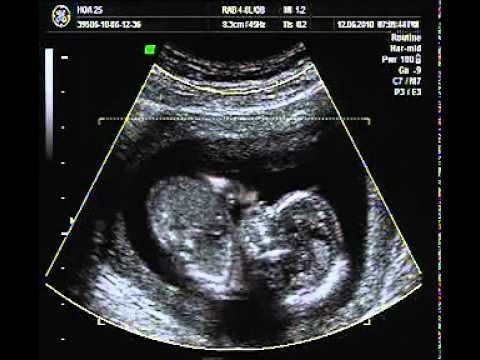

Nhịp tim không liên quan đến giới tính thai nhi mẹ nhé, để biết chính xác giới tính, mẹ nên dùng các biện pháp khác như siêu âm. Khi mẹ đi siêu âm, đặc biệt là siêu âm 4D, máy móc hiện đại, bác sĩ giàu kinh nghiệm, tư thế nằm của con thuận lợi, thì mẹ hoàn toàn có thể biết được con là trai hay gái.

Các cơ quan khác như dạ dày, ruột non, ruột già, gan, tuyến tụy... cũng phát triển nhanh và bắt đầu đi vào hoạt động. Nhờ đó, cơ thể bé yêu có thể thực hiện chức năng chuyển hóa năng lượng và bài tiết dễ dàng. Nếu thai nhi là con gái, giờ đây, buồng trứng đã có hơn 2 triệu trứng. Tuy nhiên, việc xác định giới tính dựa vào hình ảnh siêu âm thai nhi 13 tuần tuổi vẫn chưa thực sự chính xác nên mẹ cần đợi tới những tuần tiếp theo để kiểm tra chắc chắn hơn.